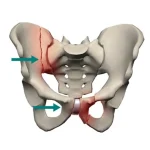

شکستگی لگن یا هیپ در کودکان، به شکستگی قسمت بالایی استخوان ران کودک گفته می شود. احتمال بروز شکستگی لگن در کودکان بسیار زیاد است، به دلیل اینکه فعالیت بدنی کودکان بسیار بالا است و ممکن است حین دویدن یا پریدن دچار مشکل شکستگی لگن شوند. اگر این مشکل به موقع درمان نشود، می تواند باعث بروز مشکلاتی مانند کوتاهی یا بلندی پا شود. عواملی مانند زمین خوردن کودک با شدت و در جهت مناسب ریسک شکستگی لگن را افزایش خواهد داد. در ادامه همراه ما باشید تا به بررسی شکستگی لگن در کودکان و راههای درمان آن بپردازیم.

شکستگی لگن (هیپ) در کودکان ممکن است در بخش های مختلف استخوان لگن در اثر ضربه شدید رخ دهد. هر چقدر فشار وارد شده به لگن شدید تر باشد، میزان آسیب وارد شده به استخوان لگن بیشتر خواهد بود. با وجود اینکهمفصل لگن یا سر ران بسیار مقاوم است و مسئولیت حمایت از راه رفتن را بر عهده دارد، اما ممکن است بر اثر سقوط، ضربه و عوامل دیگر دچار شکستگی شود. بعد از شکستگی کودک در راه رفتن و حرکت کردن دچار مشکل می شود و باید برای حل این مشکل اقدامات درمانی لازم توسط پزشک انجام گردد. در صورت عدم درمان به موقع و اصولی شکستگی لگن ممکن است عوارض جبران ناپذیری برای کودک در آینده ایجاد شود.